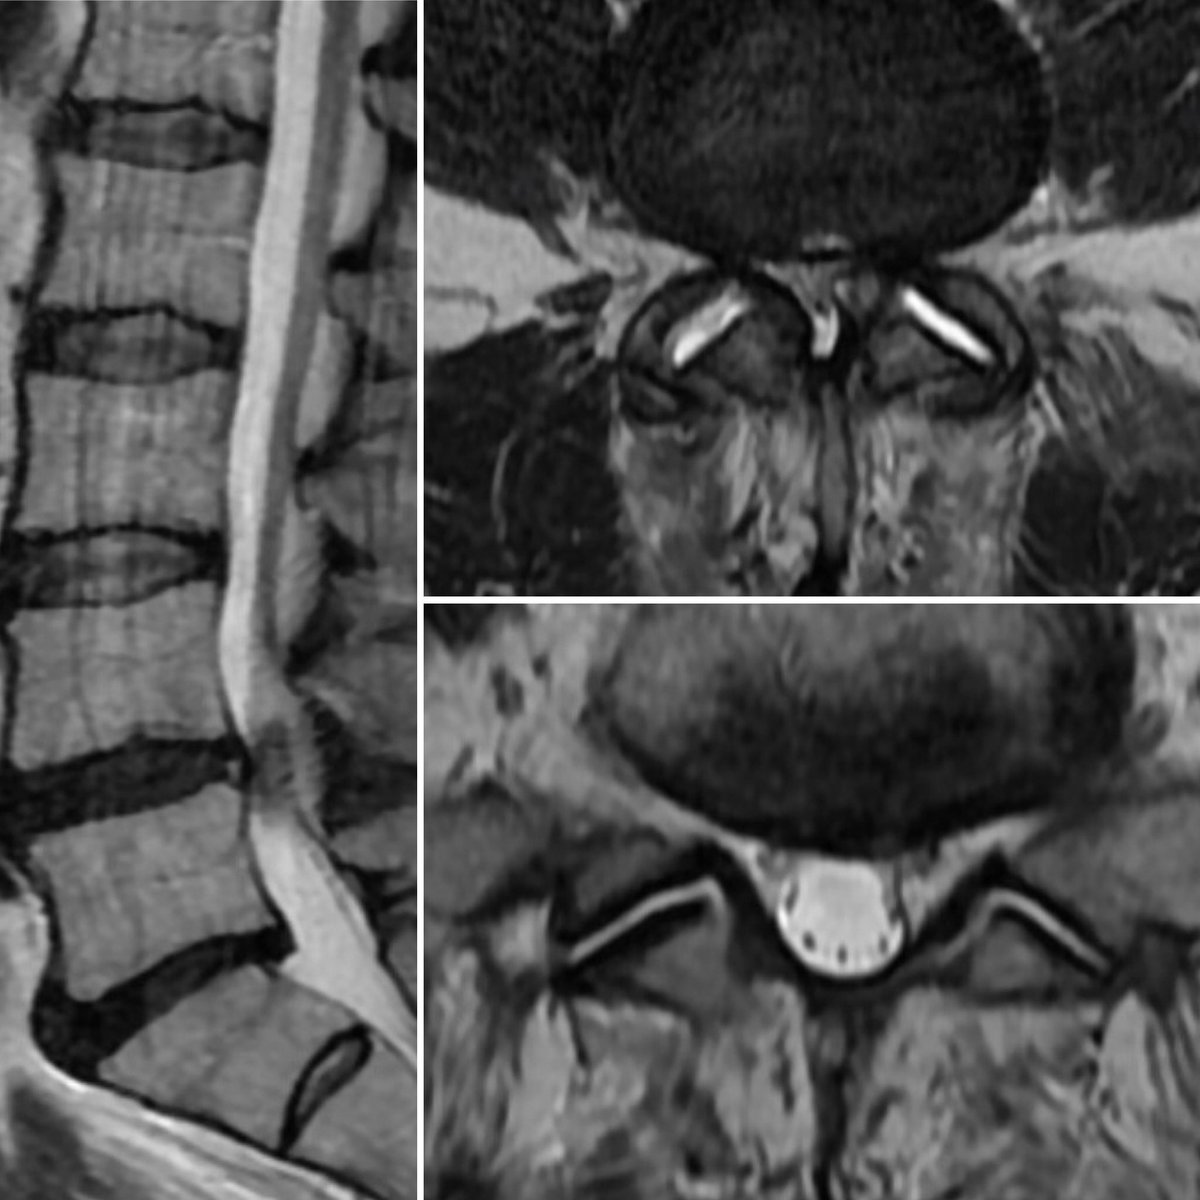

You asked for a disc herniation! This case highlights the importance of a thorough history, exam, and current imaging. L leg pain: large left L5/S1 disc MRI 18 mo later shows a left L4/5 synovial cyst with resorption of disc! No surgery. Don’t assume it’s still the same pathology